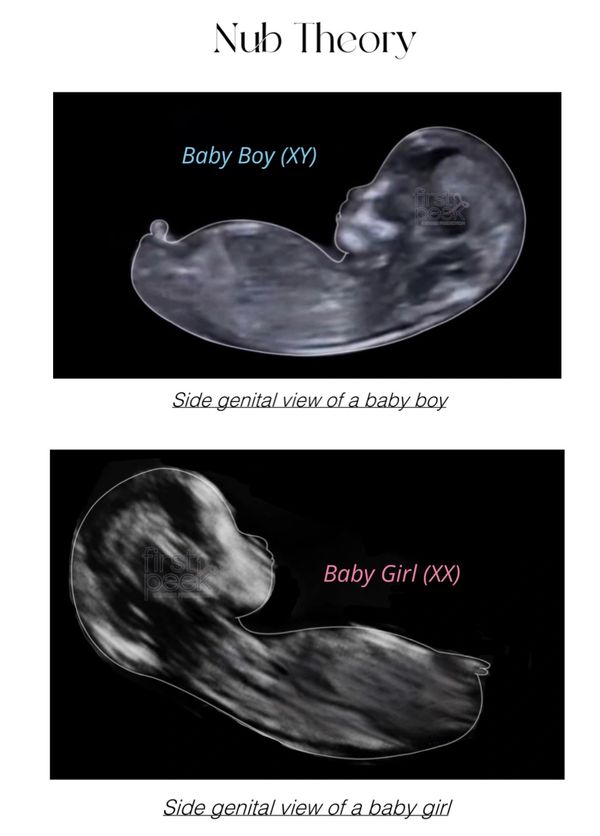

the nub theory is based on something that’s called the Genital Tubercle which is the real terminology for the Nub.

When using Nub Theory you look at the angle of the gender tubercle to help indicate the gender of your baby.

If nub is 30• degrees or above the gender of your baby is a boy.

If nub is below 30• degrees the gender of your baby is a girl.

You can use this theory starting as early as 12 weeks gestation. Sometimes the nub can been seen even well after 14 weeks gestation.

I’ve attached a little template below to show you the difference between a girl/boy nub and a percentage chart.